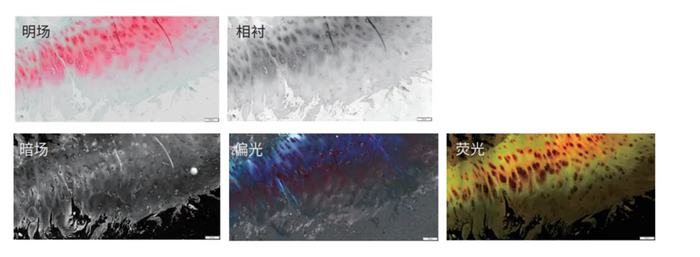

SLIDEVIEW VS200 每张玻片、每个细节、每种可能,充分释放样本潜能的应用多面手。

●轻松应对多类型样本的数字应用

通过五种成像模式为病理学样本提供了广泛的应用可能。使用偏光模式观察淀粉样蛋白样本中的晶体结构、扫描荧光染色的样本进行FISH分析或免疫肿瘤学分析等。

●适用于不同尺寸的载玻片规格

系统支持多种类型、尺寸和染色方式的玻片。系统可自动识别不同格式的玻片并在同一批次中进行扫描,从而提高了检测效率和处理通量。